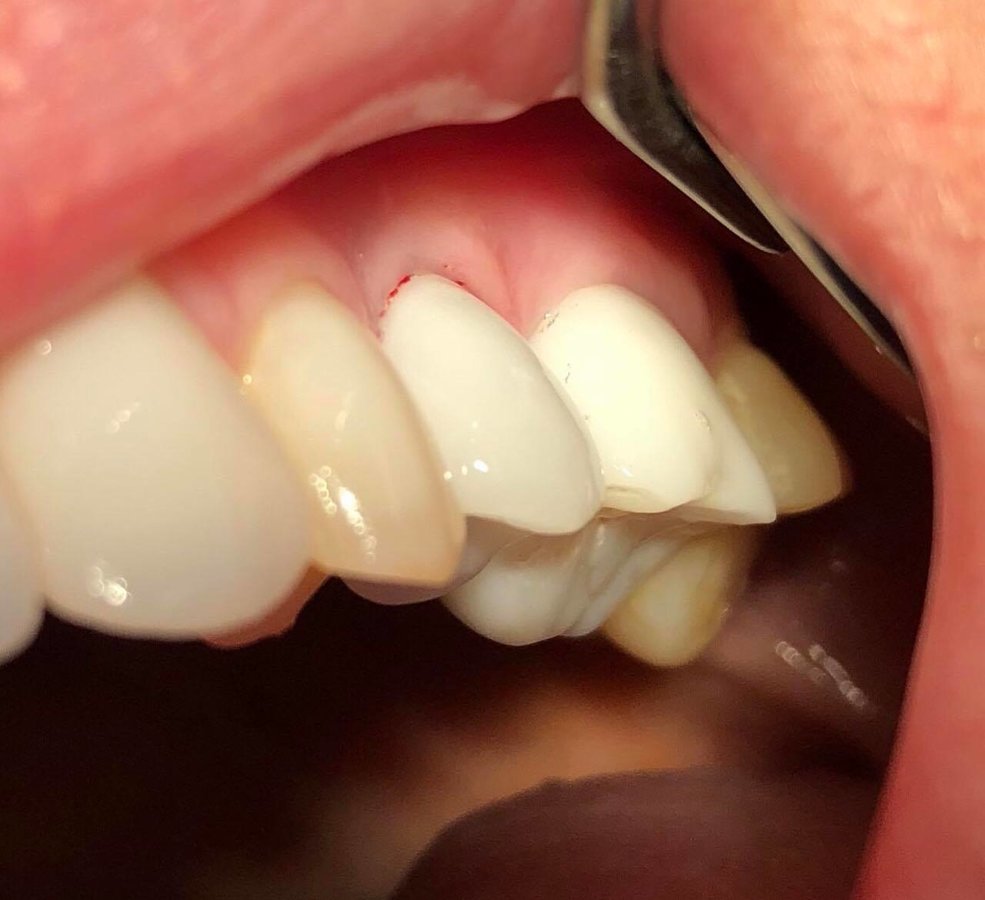

Dental Crowns $139

Veneers $334